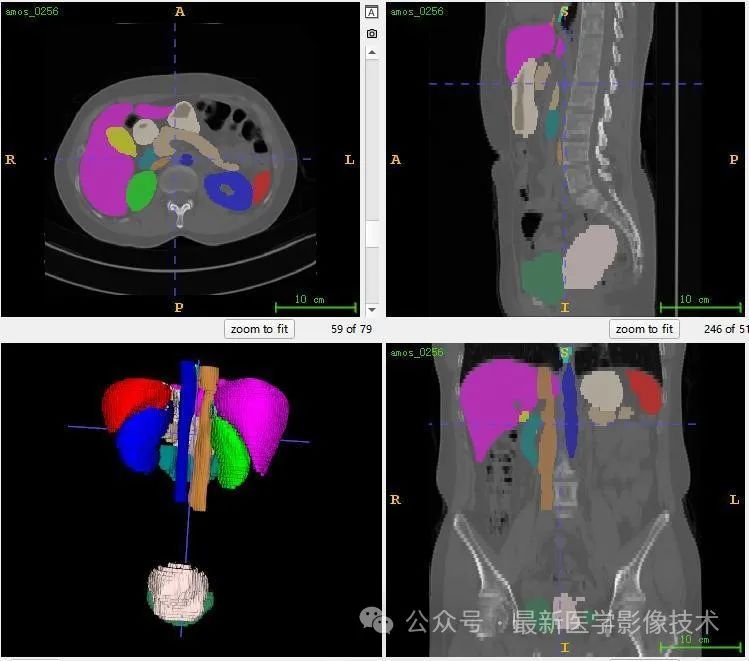

13、测试集分割结果

12、验证集分割结果

左图是金标准结果,右图是预测结果。